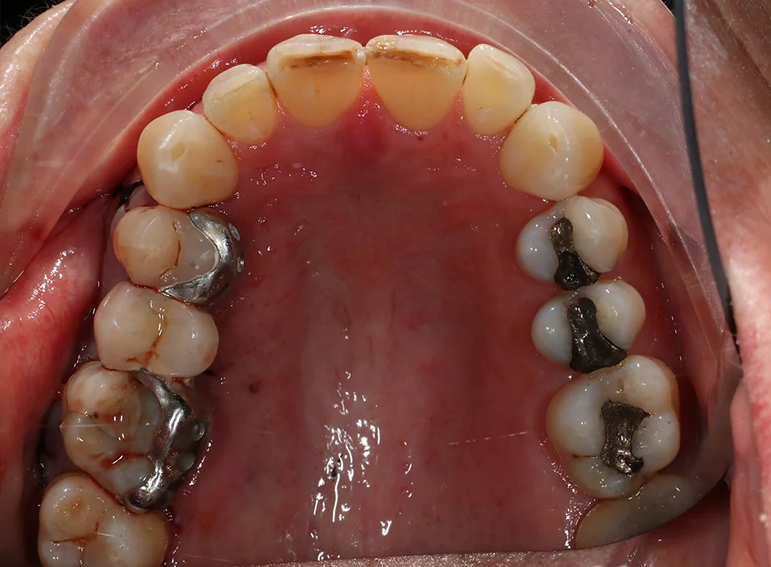

Removal of infected premolar and replacement with a temporary adhesive bridge and implant.